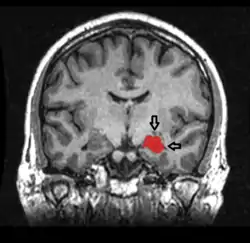

![]() Secțiune coronală făcută cu ajutorul RMN-ului. Hipocampul e colorat roșu | |